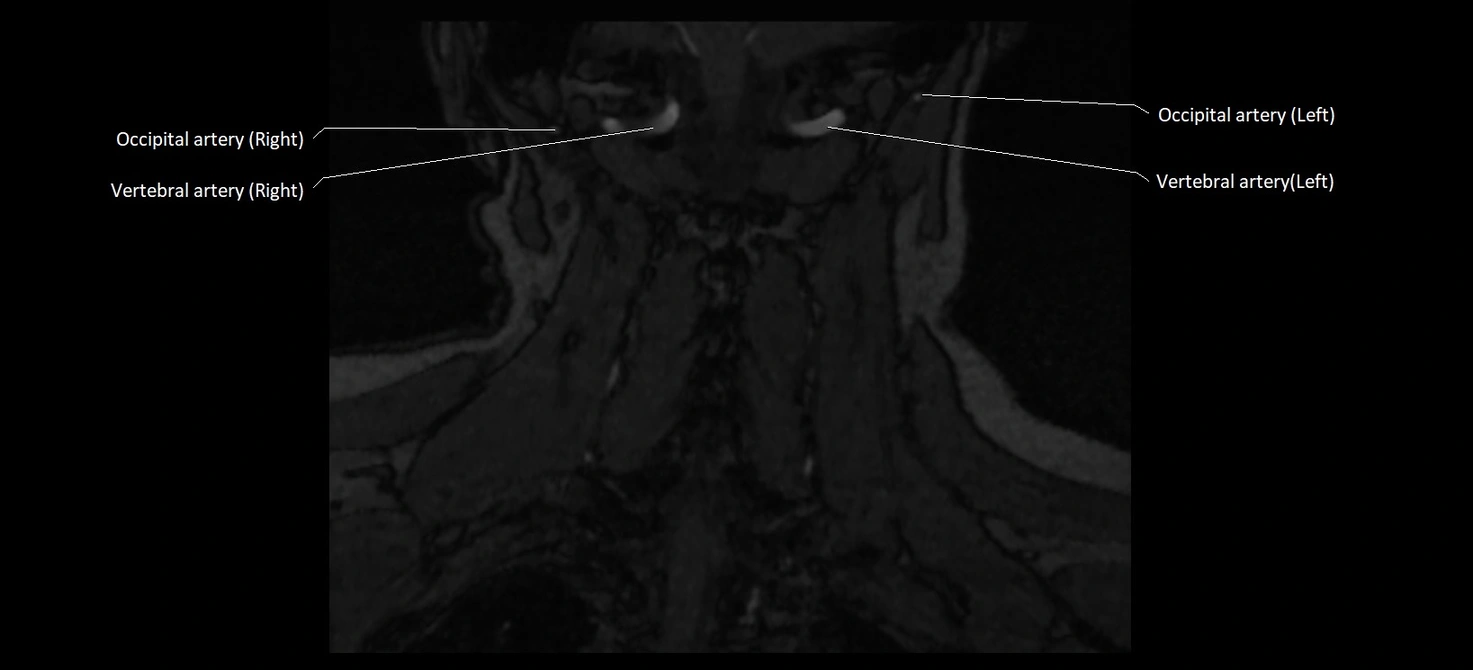

MRI images

image